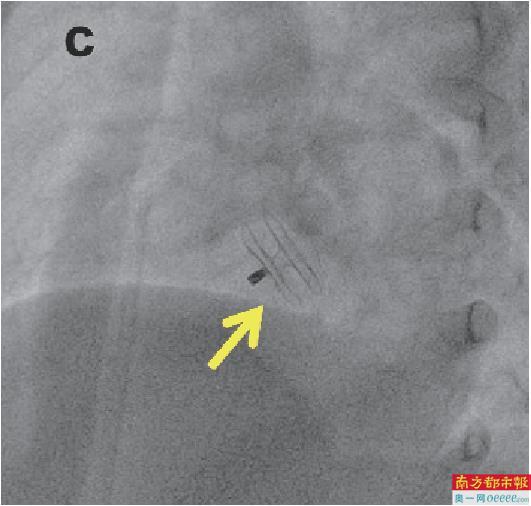

(c)传统金属封堵器植入后X线影像。箭头所示为封堵器,在X线影像上可降解封堵器几乎不可见。